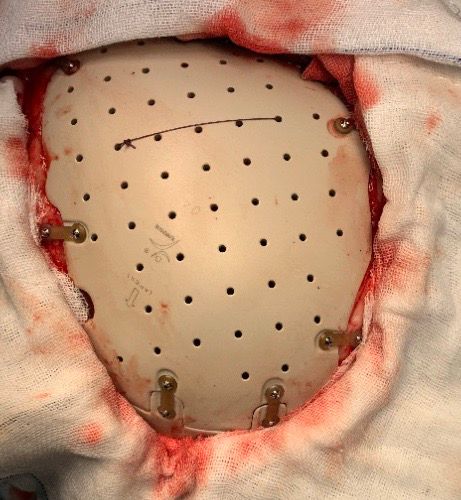

患者于2020年11月11日患者来我院继续行康复及高压氧治疗。经过系统规律的康复与高压氧治疗,患者身体状况日渐好转,并与2月27日行颅骨修补术,家属考虑患者年轻,选择了新型的聚醚醚酮新型材料。术后患者继续恢复治疗。

聚醚醚酮材料的特点在于:无毒、质轻、耐腐蚀,是与人体骨骼最接近的材料,塑型后能更好恢复头颅外貌。